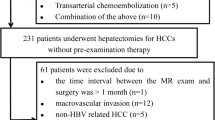

The retrospective study was approved by the Institutional Review Board, and written informed consent was waived. After computerized search of the medical data, a total of 156 patients with histologically-proven HCC were included. All patients underwent liver MRI between April 2014 and November 2015 at our institution. We retrospectively assessed the images and clinical data of these patients and 106 chronic HBV patients (94 males and 12 females; age range 28–78 years; mean 50.9 ± 1.1 years; BMI 22.2 ± 0.3) with 109 pathologically confirmed HCCs (size range 14–150 mm; mean 47.9 ± 2.9 mm) were included in the final assessment (Fig. 1). The time interval between MR exam and surgery ranged from 1 to 28 days (mean 8.7 days). Fifty patients were excluded for the following reasons: (a) the needle-biopsy results may not truly reflect the accurate histologic HCC grade because HCC is heterogeneous and often contains different histologic grades (n = 5) [10], (b) previous transcatheter arterial chemoembolization (n = 18), (c) underlying risk factors other than HBV infection alone (n = 5), (d) the time interval between the MR examination and surgery was greater than 1 month (n = 1), (e) the lesion size was below 1 cm thereby increasing the possibility of partial volume effects affecting accurate tumor grading [21] (n = 11), (f) extensive necrosis and hemorrhage meant that no enough measurable area was present (n = 2), (g) slice misregistration or distinct motion artifacts which interfered with image interpretation (n = 8).